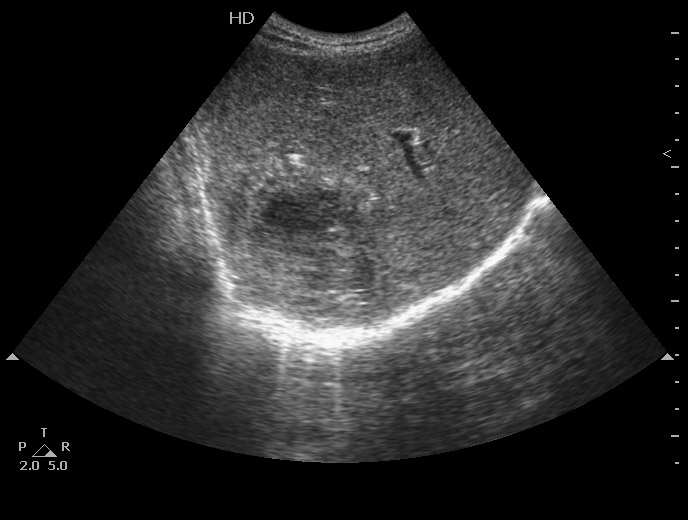

#6

Пожилой мужчина, мы ему уже дренировали абсцесс левой доли печени как минимум полгода назад.

Опять температура, симптомы интоксикации.

В левой доле определяется один крупный и несколько мелких абсцессов.

12-07-19-113514_5813_0.jpg

12-07-19-113514_1.jpg

12-07-19-113514_5813_2.jpg

Больший абсцесс задренирован, мелкие раздренировались самостоятельно в бОльший.

У него же, по-видимому, мелкие протоковые конкрменты: